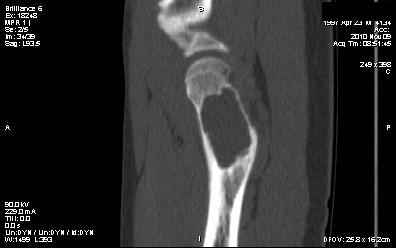

Мальчик 13 лет. В течение нескольких месяцев беспокоят боли в левом тазобедренном суставе.

При обследовании выявлена киста шейки левого бедра с сопутствующими изменениями в головке

бедра, которые мы трактуем как дистрофические. Планируем вскрытие и санацию полости кисты